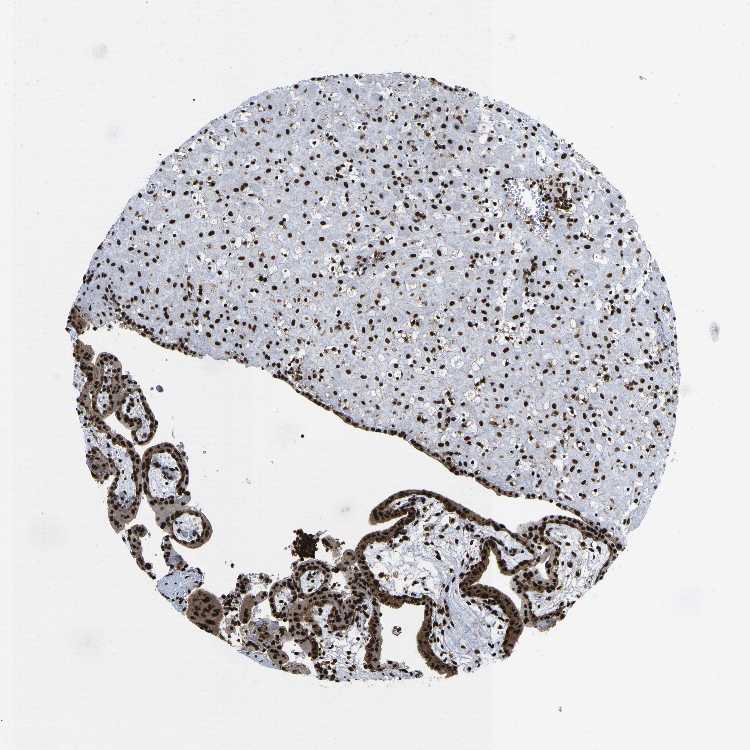

PLACENTA